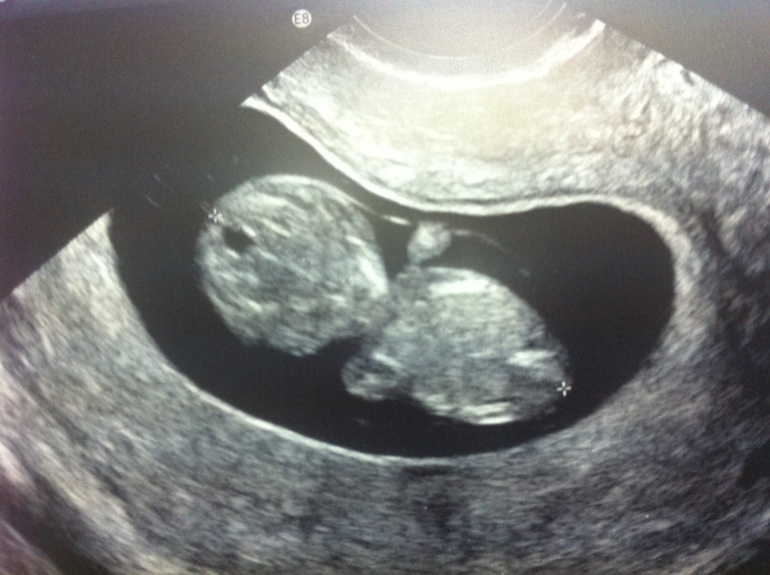

Наши 10 неделек :)

) но ВСЕ ОТЛИЧНО !!! Ктр 32, чсс 130-140 ударов в минуту

На узи показали как шевелится, включили в 4D проекции, это так круто !!! Не укладывается в голове, он/она там шевелится, а я ничего не чувствую ! %) Через пару неделек пойду туда на скрининг ( в моей жк не получилось на нужную дату записаться :( ) обязательно запишу на диск шевелючки !!!

Вот моя котлетка !!!